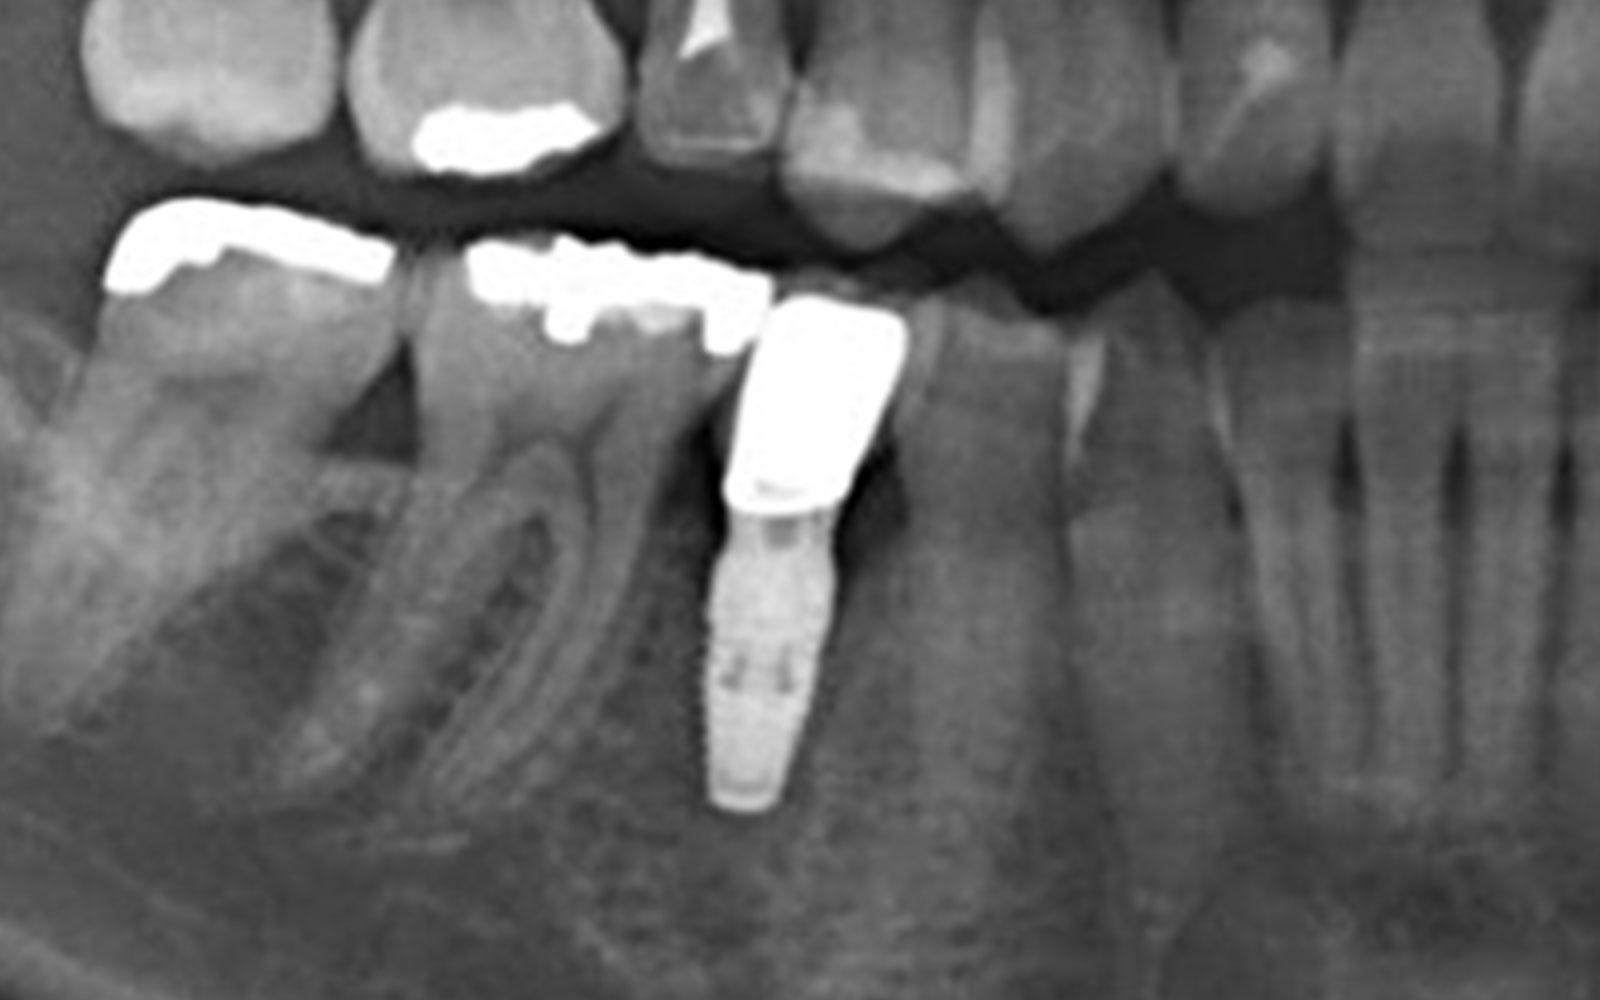

治療後

初診時

この方も左下4番の歯根破折です。7番目の歯は歯周病でグラグラな状態なのでインプラント2本埋入してます。

治療前

埋入後すぐに仮歯を入れたので術後当日より物が咬めるようになりました。